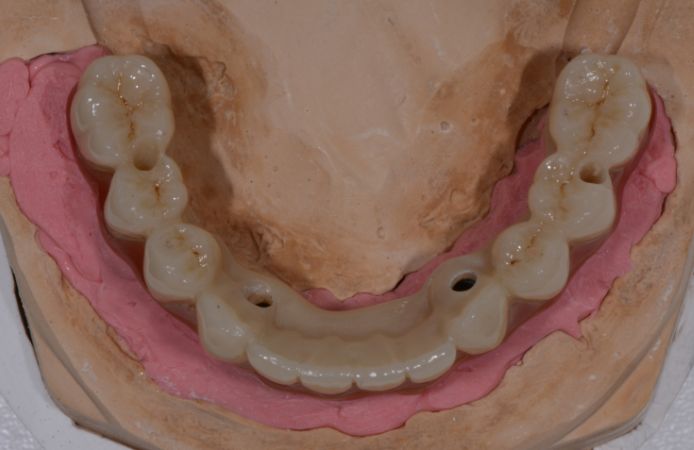

Figure 1.

Figure 2.

Figure 3.

Figure 4.